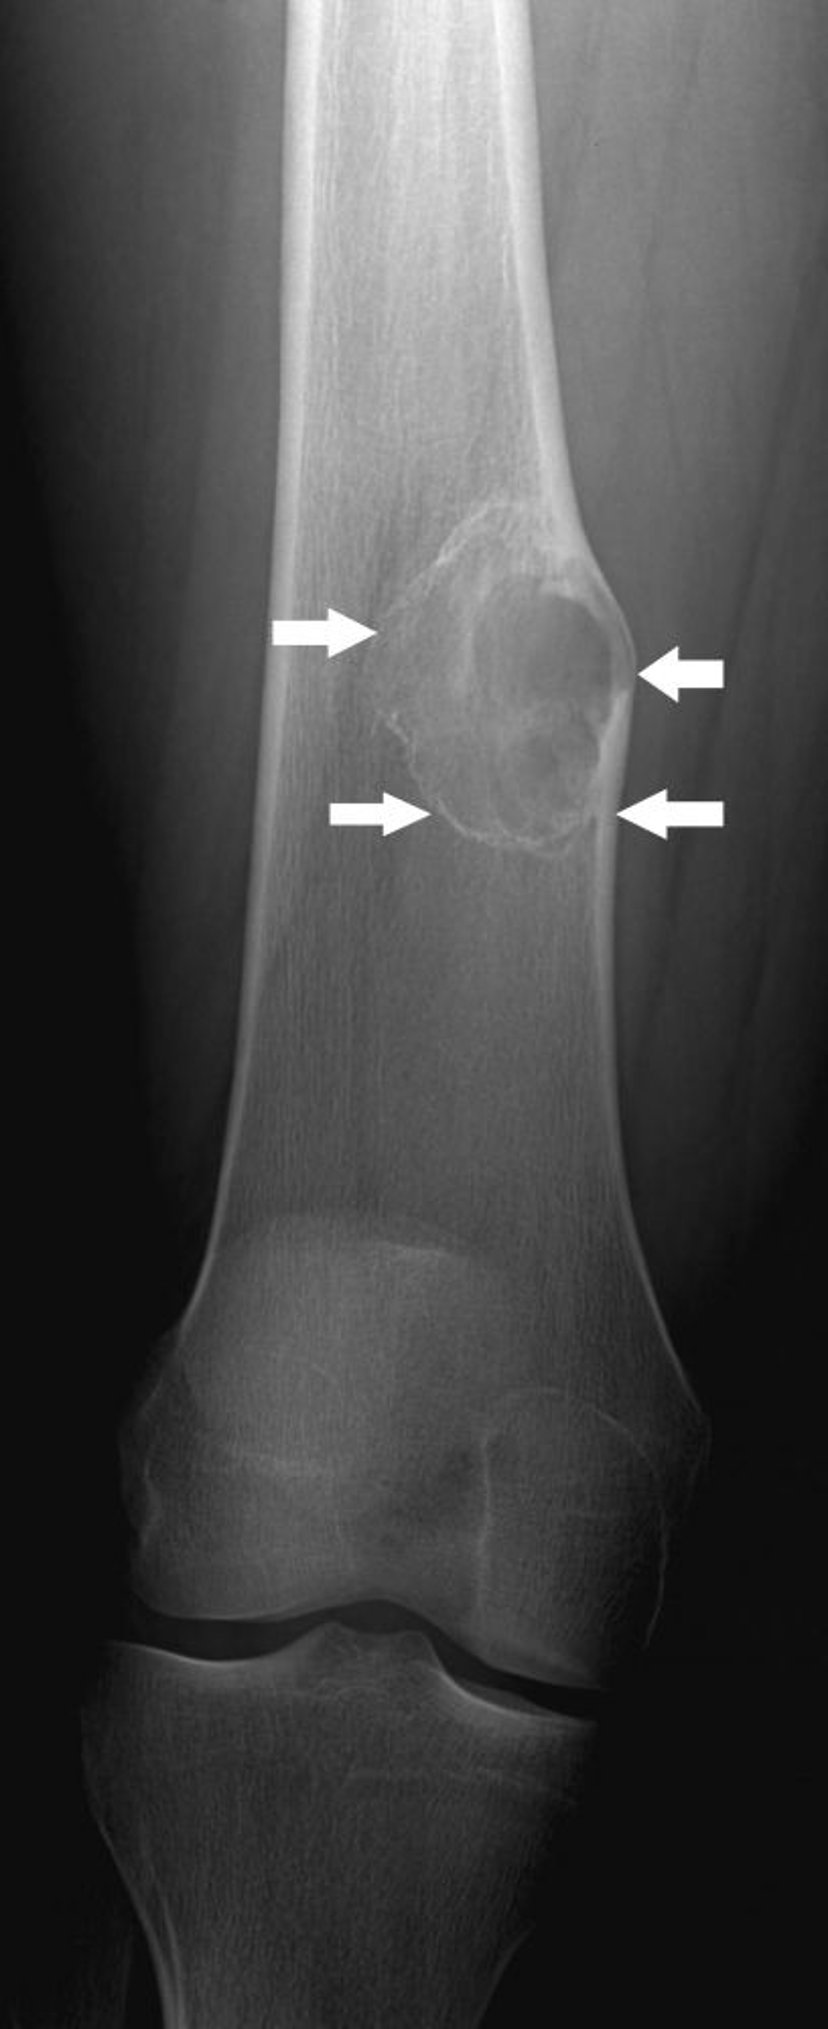

被骨化性線維腫

このX線写真には,膝関節上方の大腿骨の中に,非骨化性線維腫の特徴である軽度の拡張を伴う骨病変(矢印)が認められる。

Image courtesy of Michael J.Joyce, MD, and Hakan Ilaslan, MD.